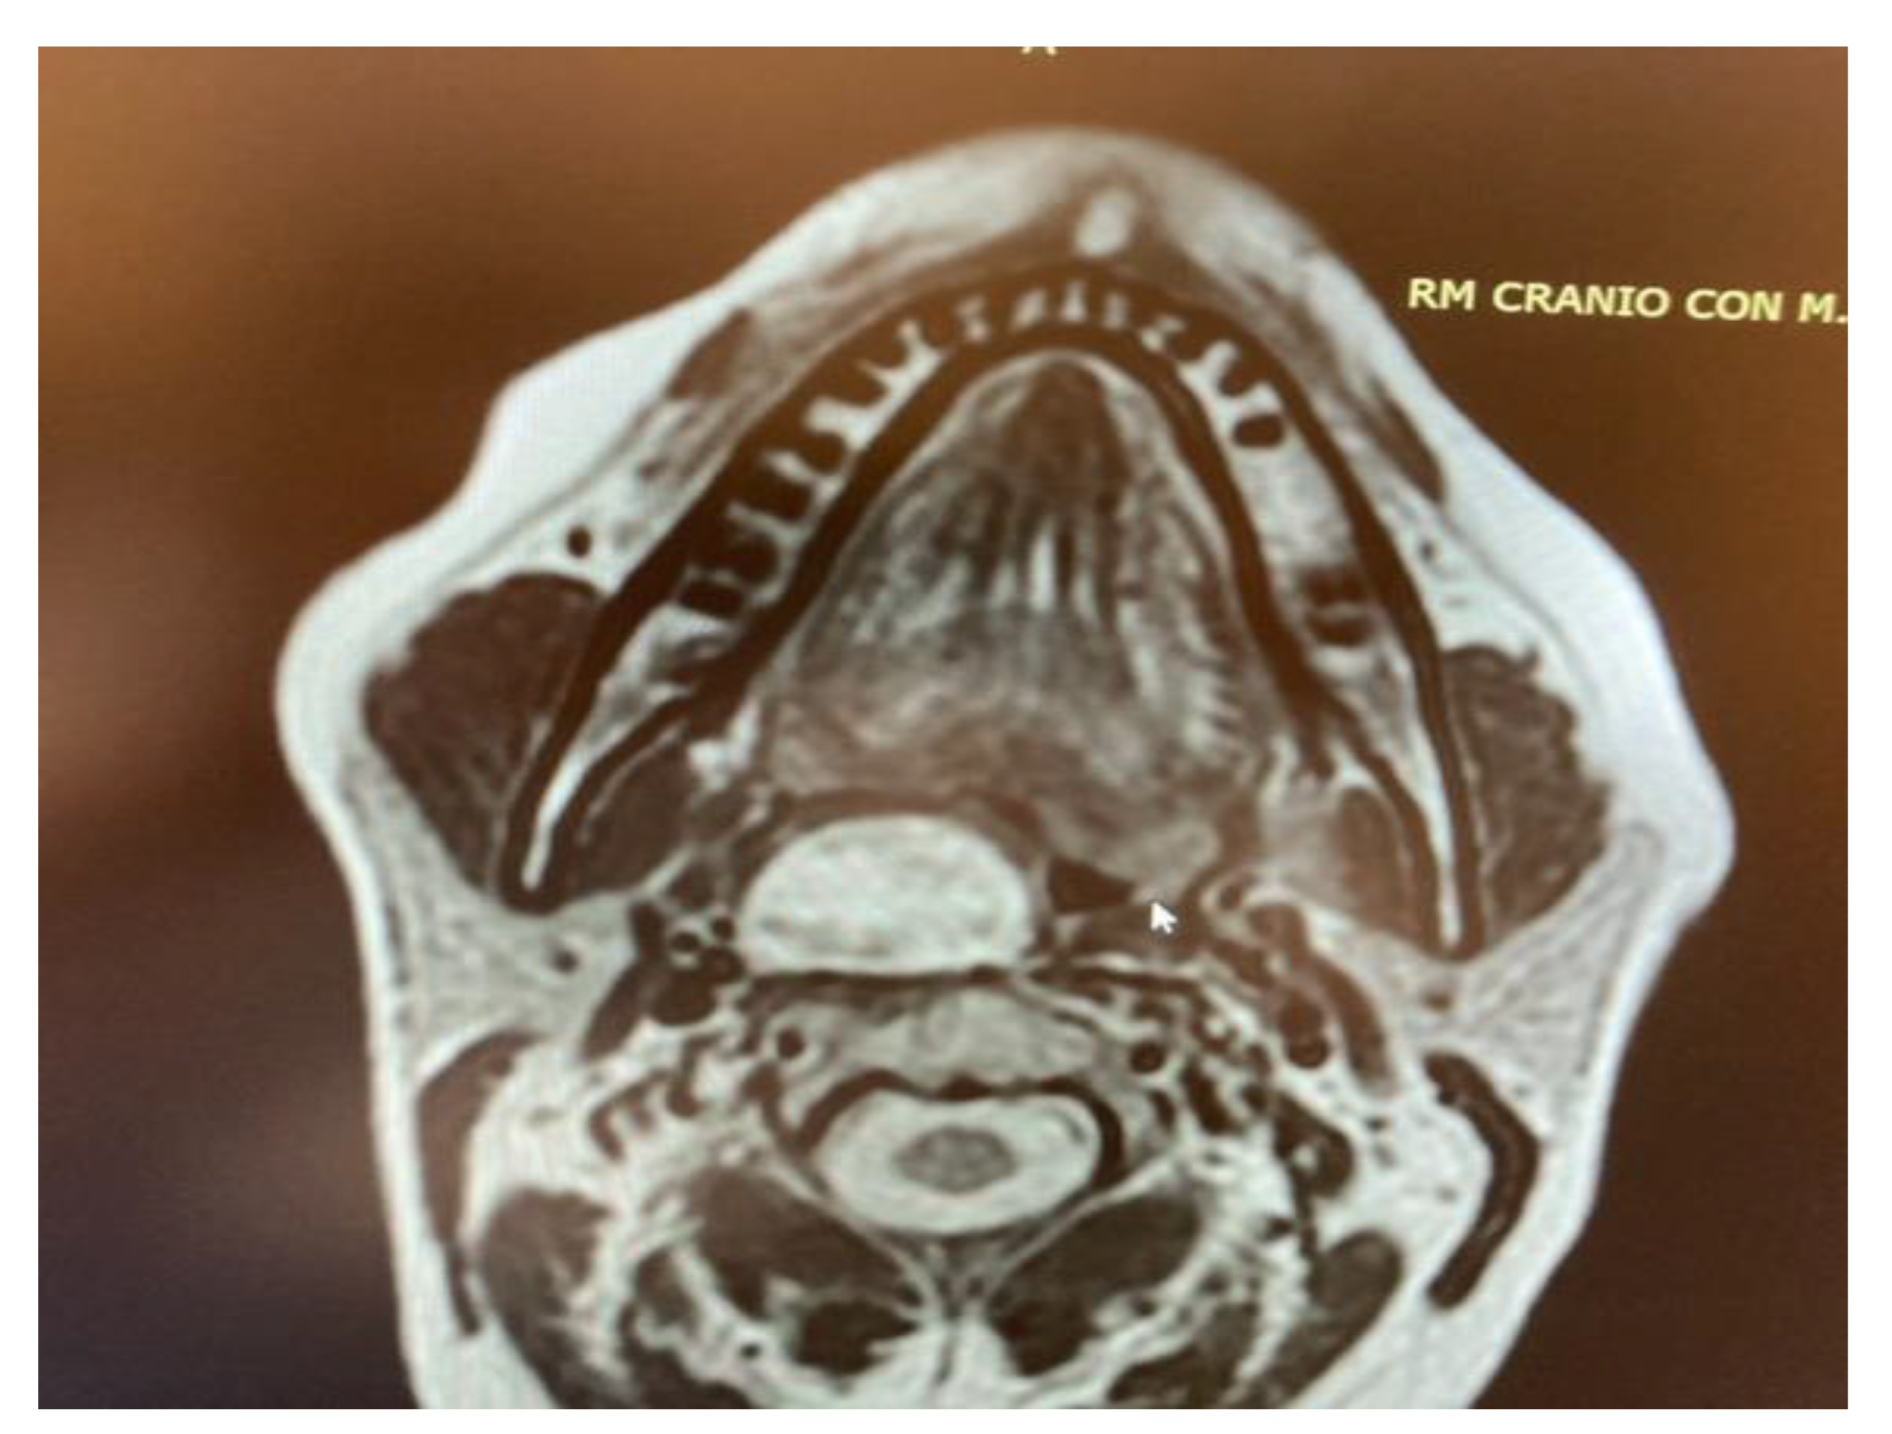

- Two schwannomas (Figure 5) originating from the cervical sympathetic chain and that arose in the superomedial aspect of the PPS, medially to the carotid sheath. The first patient underwent surgery in 2008, the second in 2019. No complications were observed during surgery and no tumour recurrence has been observed after 14 and 4 years, respectively. The only long-term complication observed was Horner syndrome (Figure 6), despite the continuity of the nerve not being interrupted. The hospitalisation time was three days for both patients.

Figure 5. MRI T2 weighted image showing a right parapharyngeal schwannoma arising from the cervical sympathetic chain. The schwannoma does not dislocate the big vessels in the typical anterior direction, but the big vessels’ dislocation is posterolateral. However, the parapharyngeal fat pad is dislocated in an anterior direction, and this suggests a carotid space tumour.

Imaging exams such as CT, and especially MRI, are necessary for the choice of the correct surgical approach, providing important information regarding the relationship of the tumour to surrounding structures, including the internal carotid artery, the internal jugular vein, the parotid gland, cranial nerves IX–XII and the distance from the skull base. Based on their variegated nature, MRI is crucial for highlighting the different features of PPS tumours: Pleomorphic adenomas are hypointense in T1 and hyperintense in T2. Schwannomas are isointense or hypointense in T1, with high enhancement with gadolinium, and hyperintense in T2, just like pleomorphic adenomas, from which they differ due to the different sites of origin and different patterns of fat and vessels dislocation. Other neurogenic tumours of the carotid space that need to be identified and distinguished from schwannomas are paragangliomas: These tumours have the characteristic “salt and pepper” aspect on T2 weighted images due to the presence of flow voids. Flow voids are indicators of a highly vascularised mass so that, in tumours with these features, a transoral approach is contraindicated due to the high risk of uncontrollable and unmanageable haemorrhage [3]. Importantly, it is possible to determine, using imaging exams, the site of origin and the potential nature of a PPS tumour, evaluating the direction of the parapharyngeal fat pad dislocation [3,6]. Parotid gland tumours tend to dislocate the parapharyngeal fat pad anteromedially; masticator space tumours tend to dislocate it posteromedially; carotid space tumours tend to dislocate it anteriorly and pharyngeal tumours dislocate it posterolaterally. The PPS fat pad is dislocated by PPS tumours, as are the great vessels that pass through this space, with anteromedial displacement of the carotid sheath structures in carotid space tumours and posterolateral displacement of the carotid sheath structures in tumours arising from the true PPS [3,6].

However, carotid space tumours do not always lead to anterior displacement of the great vessels. It is possible, as demonstrated by the schwannoma cases presented herein, that cervical sympathetic schwannomas may lead posterior displacement of the great vessels, just as parapharyngeal tumours arising from the true PPS [29]. In these cases, it might be helpful to look at parapharyngeal fat pad dislocation, which in carotid space tumours is anterior, even when the vessels are dislocated posteriorly (Figure 5). Due to the suprahyoid location, the superomedial position of the tumours and the posterolateral dislocation of the internal carotid artery, a transoral approach was preferred in both cases. Larger, clearly circumscribed tumours, even those involving the carotid space, can be removed transorally with an acceptable safety profile, but only if the big vessels are dislocated posteriorly [7,30]. This approach provided a good visualisation for the en bloc resection of both tumours and better exposure than the one achieved by a transcervical technique. After surgical removal of these tumours, Horner syndrome is frequently observed as an inevitable sequela due to the specific nervous origin of the tumour, even when an intracapsular dissection is performed [31] (Figure 6).